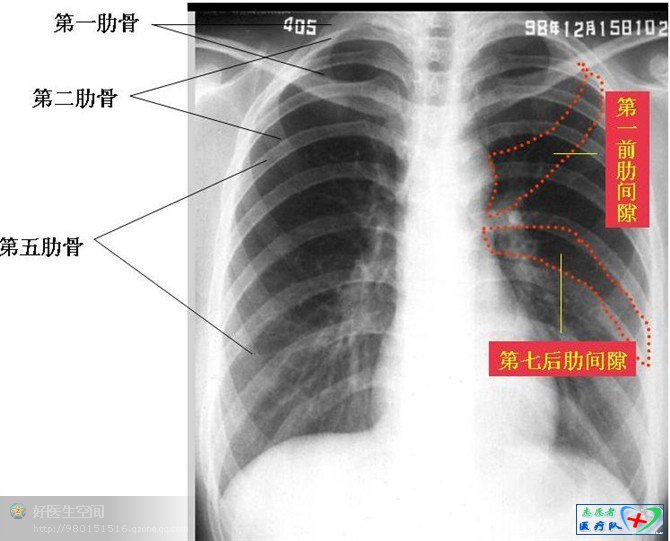

B( Bone)胸部骨骼

前有胸骨,前上方有锁骨,后有胸椎,自后向前构成胸骨支架的12条肋骨,肋骨前端为肋软骨,与胸骨相连。正常情况下,看不到肋软骨,但可以清楚看到骨骼的形状、骨皮质、骨髓质及骨纹理等。正常胸片肋骨从后上向前下数,第一肋与锁骨围成一个类圆形的透亮区,这一部分也是肺尖所在的区域,两侧对比有利于发现肺尖的病灶。如发现骨质破坏,常见为骨癌或转移癌、骨结核。骨骼的断裂,常见于外伤性骨折。成年后肋软骨逐渐钙化,尤其是第一、二软骨头钙化,有时形成片状或空洞形阴影,勿认为肺内疾病。另外,肋骨有正常变异,应仔细辨别。